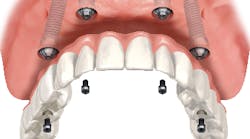

Chewing efficiency is greatly affected by how much of the teeth or bridgework in a given arch is fixed to the jawbone. Just as a person with a wooden leg would not walk as well as a person with a hinged and fitted carbon fiber prosthetic leg, a person with a tissue-supported denture will not chew as efficiently as a person with implant-supported bridges that are fused to the jawbone (figure 1).

A person chewing with upper and lower dentures will only achieve 20% (an average of 30% for the upper denture and 10% for the lower) of the chewing efficiency of a person chewing with a full set of natural teeth, whereas a person chewing with upper and lower implant-supported bridges will achieve 90% chewing efficiency (figure 2). (2)The ability to extract additional nutrients from the food bolus can have a significantly positive impact on a patient’s overall health. Studies have tied the use of implant-supported bridges versus dentures to an increase in life expectancy of seven years. (3) To maximize a patient’s health and reduce future costs, it is important to use a fixed prosthesis versus a removable one.